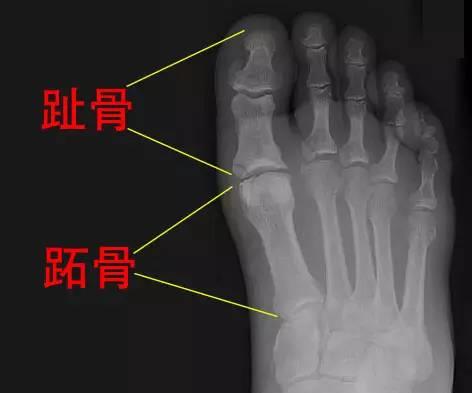

第二趾比第一趾长的“希腊脚”看上去很美,但如果第二趾比第一趾长0.5厘米以上就可能是莫顿趾,又称莫顿综合征。

这是因为第一趾的跖骨特别短,导致走路和跑步时第一趾的受力被转移到第二趾和第三趾,使这两个脚趾根部容易长厚茧,即俗称的“鸡眼”,而且整个脚掌受力不均衡,还可造成转移性前跖痛,以及下肢肌肉和关节的损伤,甚至引起背部和颈部的不适。严重者,如果症状严重医生会给患者设计相应的鞋垫、支具,甚至要做手术治疗!!!